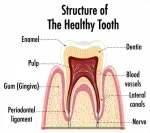

Показаниями для удаления пульпы является пульпит или глубокий кариес, в случае, если невозможно очистить полость без пульпэктомии.